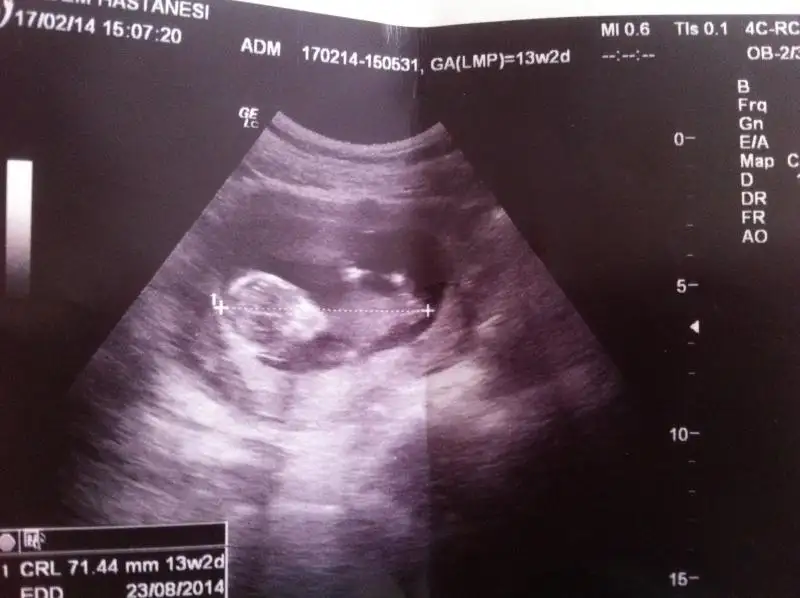

$IMG_2633.webp merhaba kızlar 13+3 haftalık cinsiyeti çok merak konusu:44: evimizde ilk bebeğimiz allah biliyor ya gönlüm hep kızdan yana sağlıklı sihatli olsun en öncelik o tabi takipteyim lütfenn benimkinde ne görünüyor dr söylemedi :50:

Kiza benziyo canim ama nubu net goremedn soyluyorum bi ihtimal

Farklı bir ultrason koymuştum ama fatoş arkadaşta ikiliem de kalmıştı, cinsiyet namında tahmin zordu biraz, hem kıza hem erkeğe benziyor demişti bu resim daha net, doktor da %85 kız demişti bu arada.. :emir_bebek::16: